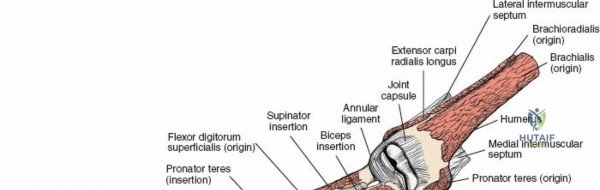

The radius and ulna function together as a highly coordinated articular quadrangle. The proximal radius consists of the radial head, which articulates with the capitellum; the radial neck; and the bicipital tuberosity, which serves as the insertion site for the biceps brachii tendon. The biomechanics of the forearm dictate that the radius rotates around the stationary ulna during pronation and supination. The normal lateral curvature of the radius—the radial bow—is critical for this rotational clearance. Any surgical approach to the proximal radius must allow for the precise restoration of this bow, as even a minor malreduction can lead to profound deficits in forearm rotation.

The anterior approach to the radius is an elegant example of utilizing true internervous planes to achieve deep exposure without denervating musculature. Distally, the internervous plane lies between the brachioradialis muscle (innervated by the radial nerve) and the flexor carpi radialis muscle (innervated by the median nerve). Proximally, the plane transitions to lie between the brachioradialis (radial nerve) and the pronator teres muscle (median nerve). Exploiting this plane allows the surgeon to mobilize the entire lateral muscular compartment (the "mobile wad" comprising the brachioradialis, extensor carpi radialis longus, and extensor carpi radialis brevis) away from the anterior flexor compartment.

Vascular Anatomy and the Recurrent Radial Leash

The radial artery runs distally through the forearm, initially lying deep to the brachioradialis muscle before becoming more superficial in the distal third. Just distal to the elbow joint, the radial artery gives off a complex network of vessels known as the recurrent radial artery leash (the "leash of Henry"). These vessels branch laterally to supply the brachioradialis and the mobile wad. To successfully mobilize the brachioradialis laterally and access the proximal radius, this entire leash of vessels must be meticulously isolated, ligated, and divided. Failure to do so will tether the brachioradialis, prevent adequate exposure, and risk severe postoperative hematoma from avulsed vessels.

Exposing the proximal third of the radius requires extreme vigilance due to the proximity of the posterior interosseous nerve. The key anatomical landmark here is the insertion of the biceps tendon. Follow the biceps tendon distally to its insertion on the bicipital tuberosity of the radius. A small bursa lies just lateral to the tendon; incise this bursa to gain initial access to the proximal radial shaft. Because the radial artery lies superficial and medial to the tendon at this level, all deep dissection must remain strictly lateral to the biceps tendon.